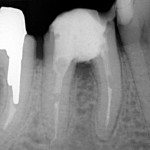

Jeśli przeleczony kanałowo ząb jest wrażliwy a zdjęcie rentgenowskie wykazuje defekt kostny w obrębie bifurkacji  czyli w miejscu rozdzielenia korzeni, wszystko wskazuje na to, że dno komory zęba jest zniszczone, a nieszczelnośc ta spowodowała zniszczenie kości w tym miejscu. Zachowawcze leczenie jest niemożliwe.

Jeśli chce się uratowć taki ząb, jedynym rozwiązaniem jest separacja czyli premolaryzacja. Zabieg ten wykonuje się w znieczuleniu miejscowym. Wiertłem przecina się ząb, tak by odsłonić całą perforację dna komory. Stwarza się w ten sposób dwa oddzielne zęby. Miejsce przecięcia należy bardzo dokładnie i szczelnie zabezpieczyć kompozytem. Jest to dość trudne w wilgotnym, podziąsłowym miejscu. Jeśli leczenie kanałowe jest nieszczelne należy je wykonać ponownie.